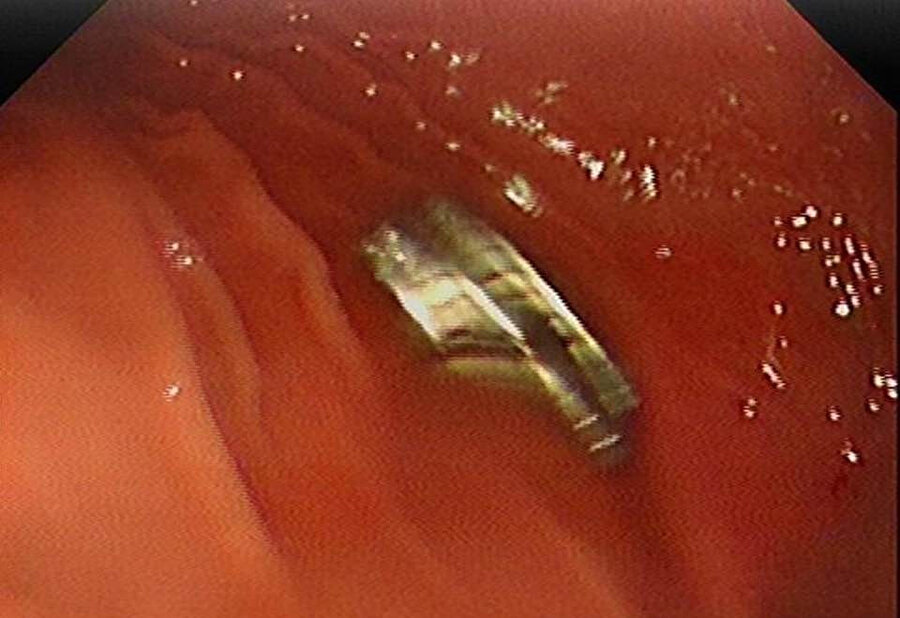

Edinilen bilgiye göre, Erzurum’da bir çocuk evde bulunan 19 tane mıknatısı yuttu. Çocuğun rahatsızlanması sonucu durumu öğrenen aile hastaneye başvurdu. Daha sonra çocuk Elazığ’a sevk edildi. Fırat Üniversitesi Çocuk Gastroenteroloji Hepatoloji ve Beslenme Bilim Dalı Başkanı Prof. Dr. Yaşar Doğan, çocuk hastanın yemek borusuna yapışmış 19 mıknatısı endoskopik yöntemle çıkardı.

Mıknatıslar uzun süre yemek borusunda takılı kaldığı için yemek borusu ve mide girişinde zedelenmeler olurken, çocuğun sağlık durumunun iyi olduğu ve taburcu edildiği öğrenildi.